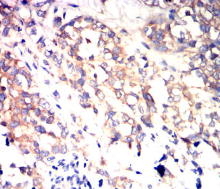

IHC    1/200 - 1/1000